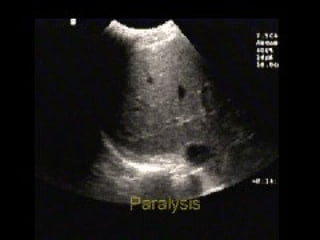

Absent lung sliding

Absent lung sliding Exaggeratedhorizontal artifacts Loss of comet-tail artifacts Broadening of the pleural line to a band The key sonographic signs of Pneumothorax